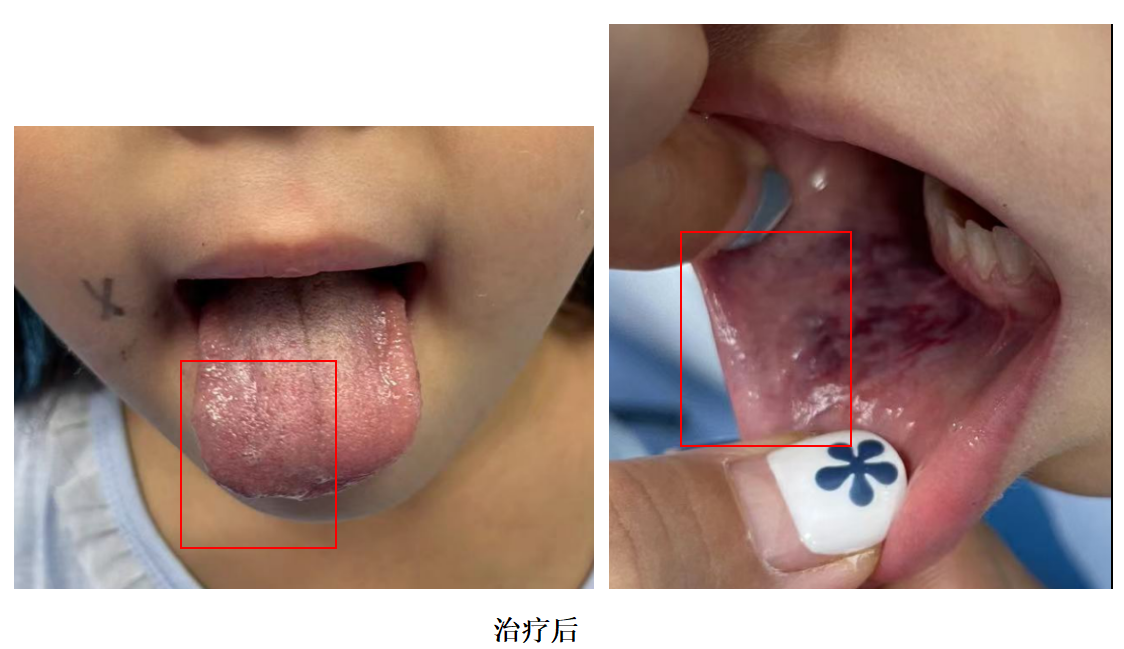

三、术后复查

孩子再次来时,包块比上次已经缩小很多,影像学也验证了临床的改善,相信再经过一段时间恢复,孩子就可以痊愈了!